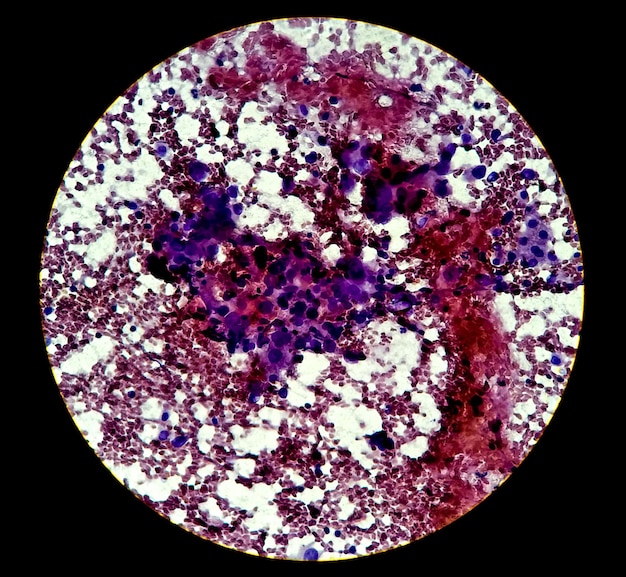

Hallaron que la mayoría de los genes asociados con un mal pronóstico, se daban por una población de células tumorales única que llamaron células de alta recaída (HRC).

Usando un ratón, simularon que sufría una recaída metastásica después de la resección quirúrgica del tumor primario. “Los HRC residuales ocultos en hígados de ratones después de la cirugía primaria de CCR dieron lugar a múltiples tipos de células a lo largo del tiempo, incluidas las células tumorales de tipo madre LGR5+2,3,4, y causaron una enfermedad metastásica manifiesta. Usando Emp1 (que codifica la proteína de membrana epitelial 1) como un gen marcador para HRC, rastreamos y eliminamos selectivamente esta población celular”, señalan en Nature.